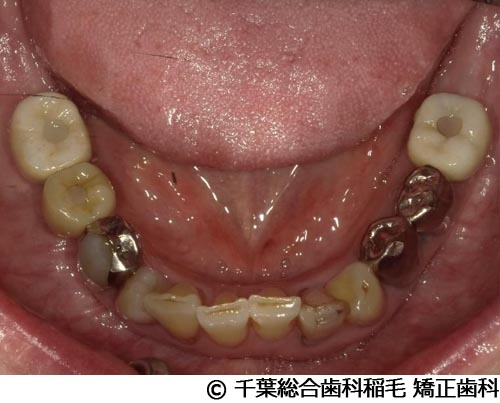

【症例2】下顎大臼歯2本インプラント埋入手術

- 治療前

- 治療後

- 治療名

- 下顎大臼歯2本インプラント埋入手術

- 費用

- 950,000円(税込)

- 期間

- 11ヵ月

治療内容

-

患者様の症状

歯茎の腫れと痛みが主訴でご来院されました。

治療法

右下第一、第二大臼歯は重度の歯周病だったため、保存が難しく、抜歯となりました。

義歯とインプラントそれぞれのメリットデメリットをお話しさせていただき、インプラントでの治療を選択されました。 -

治療結果

お痛みや腫れも和らぎ、現在も定期検診で拝見させていただいています。

※治療結果は患者様によって個人差があります。